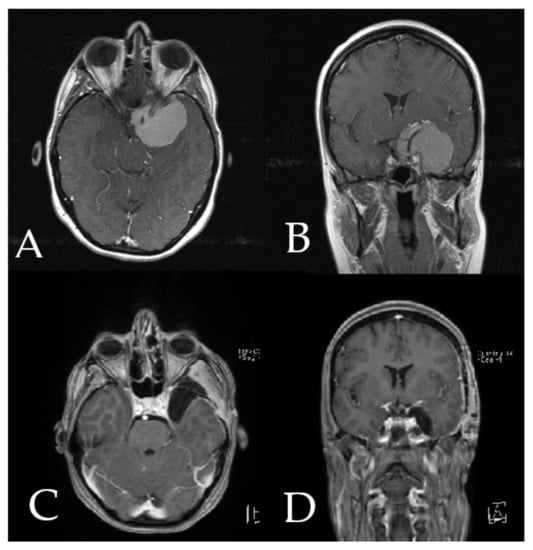

Figure 4. Navigation and AR support following complete resection of the tumor (patient no. 20). (A) Microscope video with head-up display and 3-dimensional (3D) visualization of the segmented objects (tumor in yellow, carotid and anterior cerebral arteries in blue, optic chiasm in yellow). (B,C) Probe’s eye view in 2-dimensional and 3D fashion. (D) Axial, (E) coronal and (F) sagittal views of standard navigation display with the segmented objects (focus on the sellar floor following complete resection). (G) AR display on video screen with the 3D outline of segmented structures. (H) Corresponding probe’s eye view. (I) Target view and (J) overview depicting the video plane in relation to the segmented 3D objects.